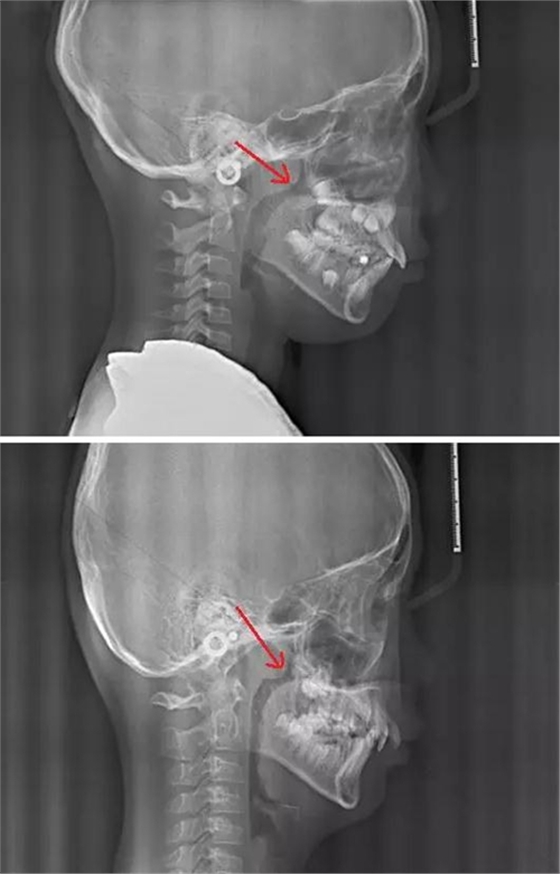

賀老師提到兒童青少年最常見(jiàn)的兩種阻塞呼吸道的問(wèn)題即腺樣體肥大和扁桃體肥大。首先我們通過(guò)頭顱側(cè)位片來(lái)了解一下這兩個(gè)腺體在x線(xiàn)片上的位置。

以下兩張標(biāo)注的是肥大的腺樣體及其位置